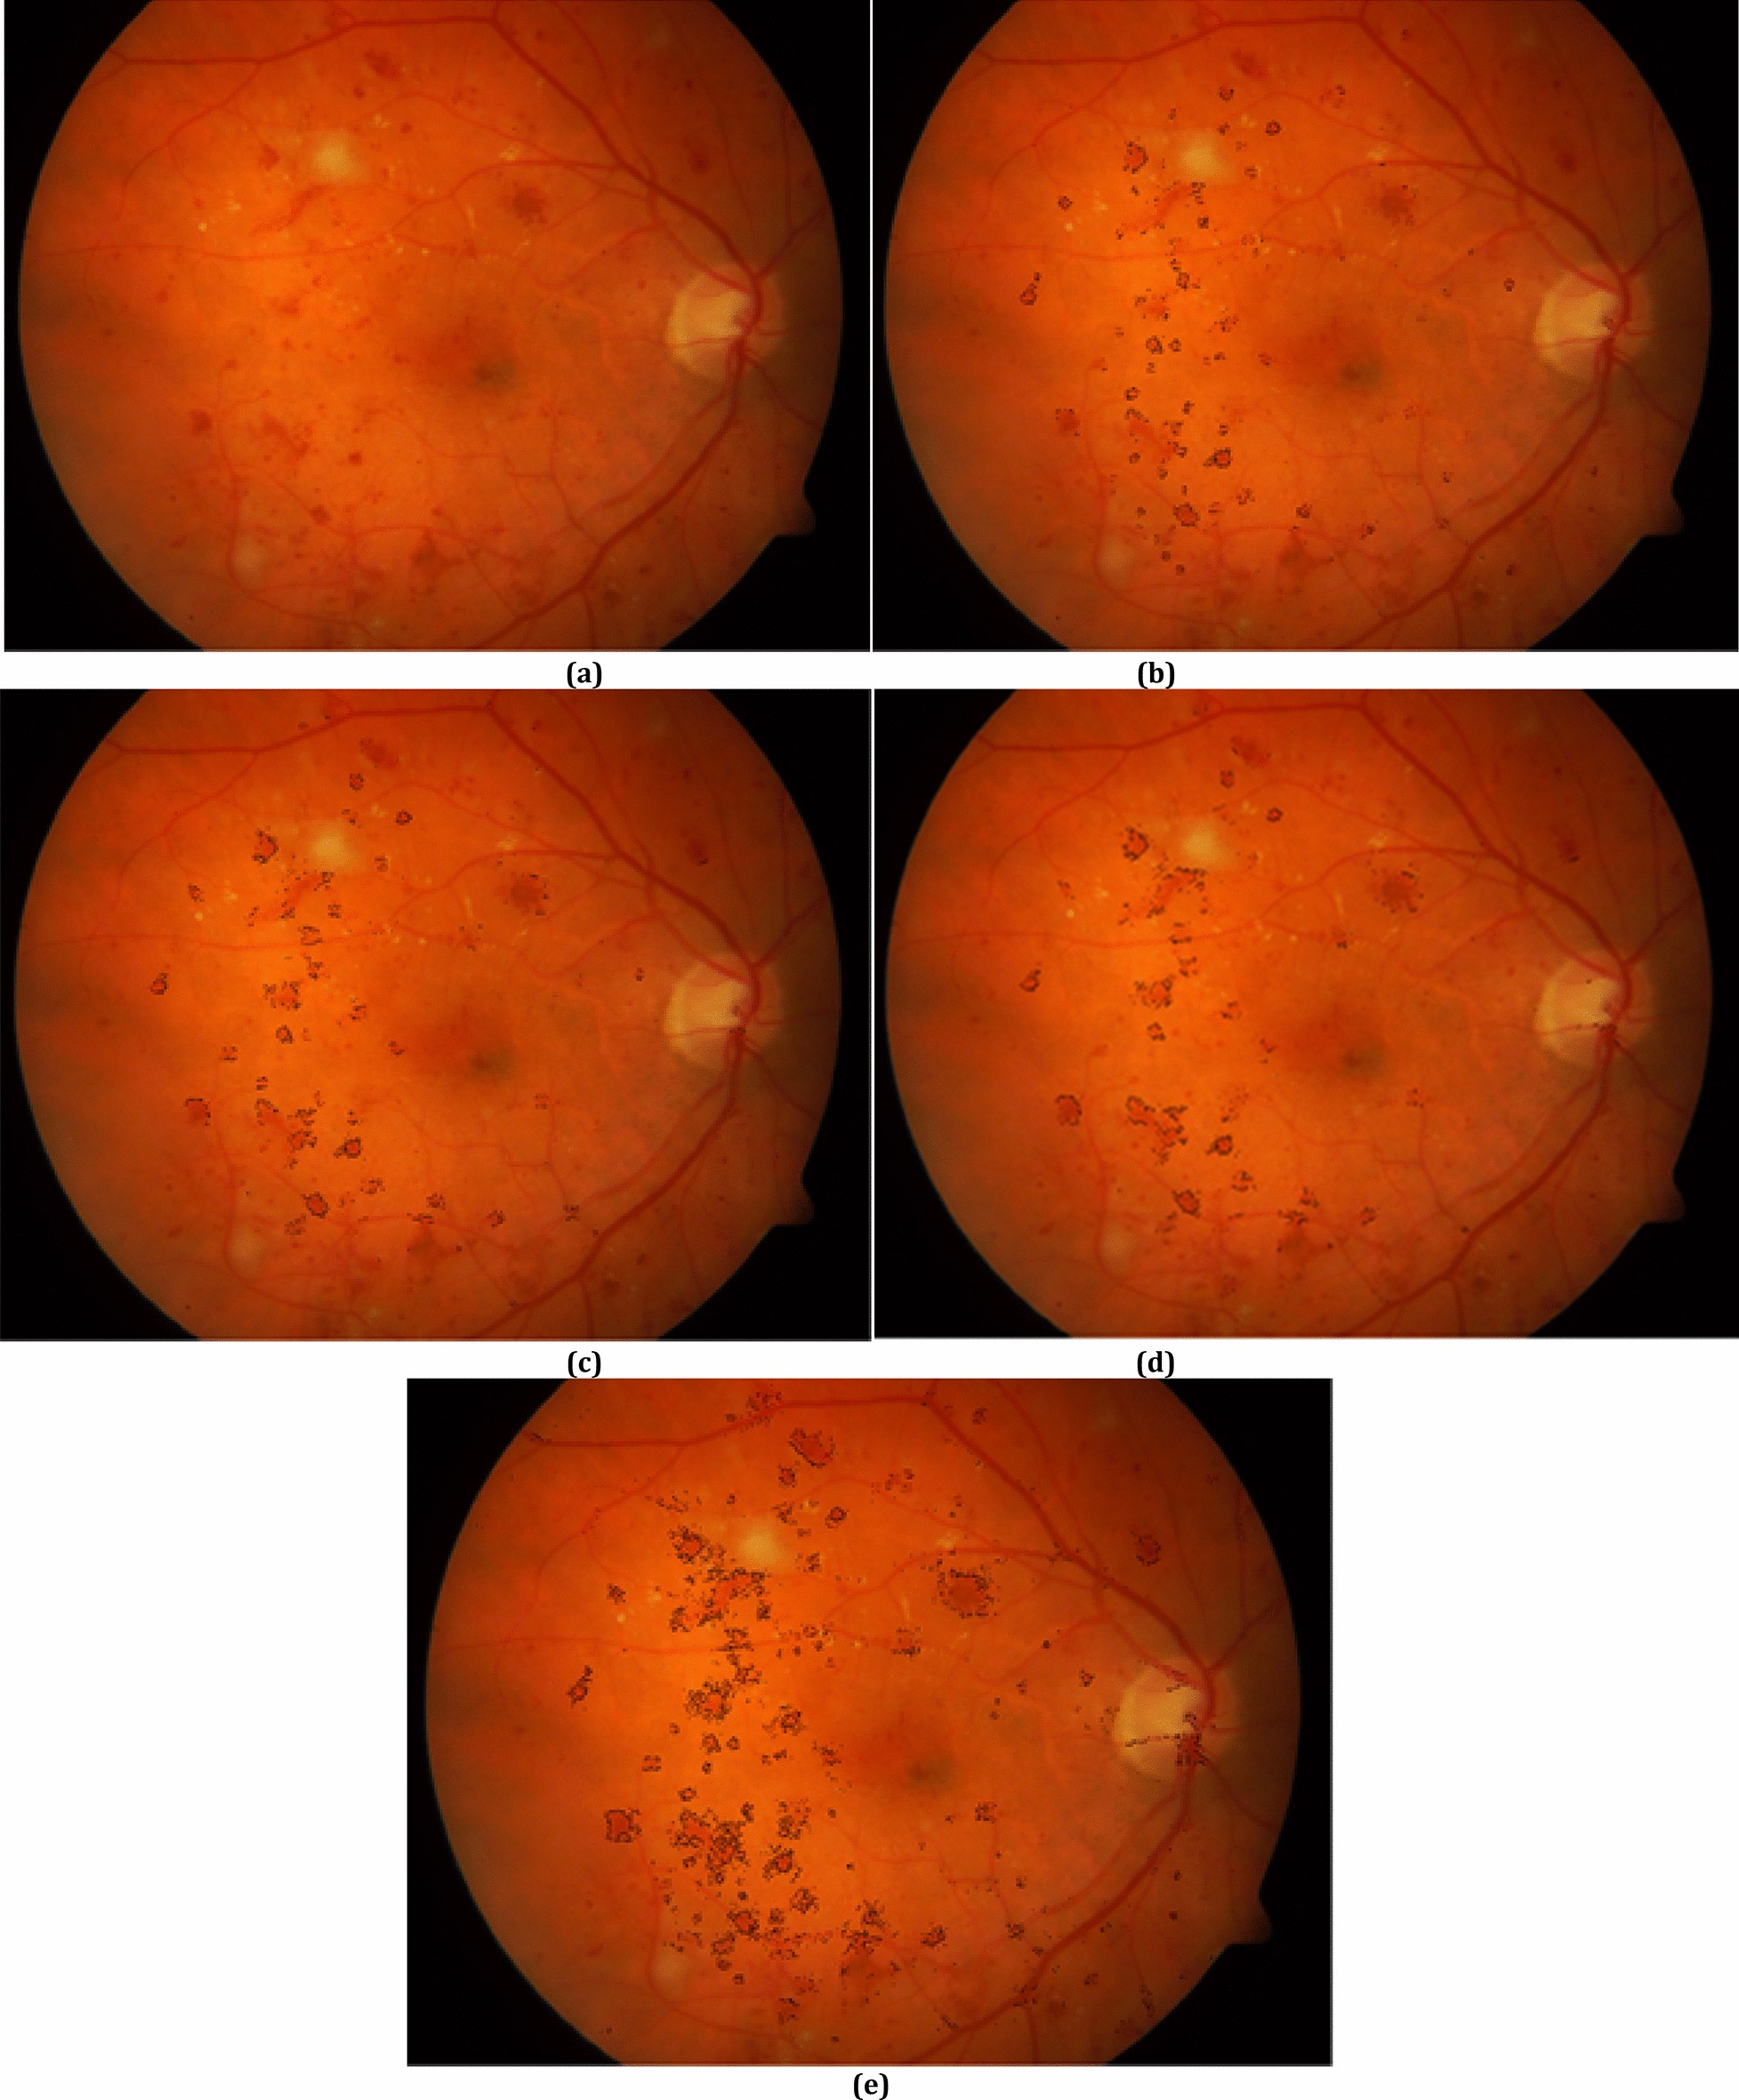

Figure 4

From: Red-lesion extraction in retinal fundus images by directional intensity changes’ analysis

(a) A fundus image, boundary pixels for red-lesions for (b) d0 = 10, (c) d0 = 16, (d) d0 = 22, (e) all boundary pixels for red-lesions.